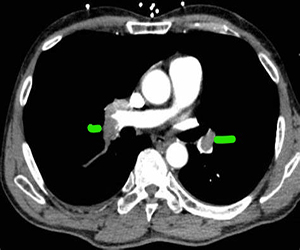

• CT pulmonary angiogram (also called a CT-PA) – Usually diagnostic